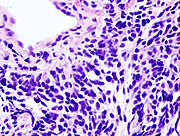

Small cell lung carcinoma (SCLC)

Small cell lung carcinoma (SCLC, also called "oat cell carcinoma") is less common. It tends to arise in the larger airways (primary and secondary bronchi) and grows rapidly, becoming quite large. The "oat" cell contains dense neurosecretory granules ( vesicles containing neuroendocrine hormones) which give this an endocrine/paraneoplastic syndrome association. While initially more sensitive to chemotherapy, it ultimately carries a worse prognosis and is often metastatic at presentation. Small cell lung cancers are divided into Limited stage and Extensive stage disease. This type of lung cancer is strongly associated with smoking.